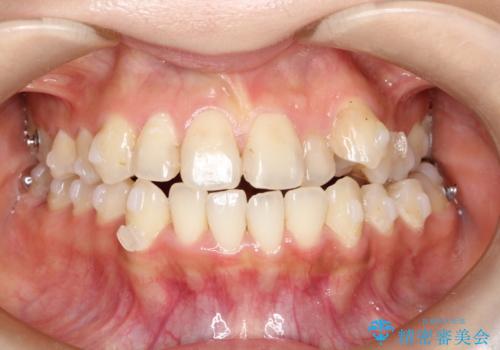

八重歯をインビザラインで非抜歯矯正

- 八重歯を主訴に来院されました。

インビザラインにて奥歯を後方に移動して八重歯が入るスペースを確保してく矯正する計画としました。

八重歯と前歯のガタガタがなくなり、歯並びがきれいになったのと、かみ合わせも改善することができました。